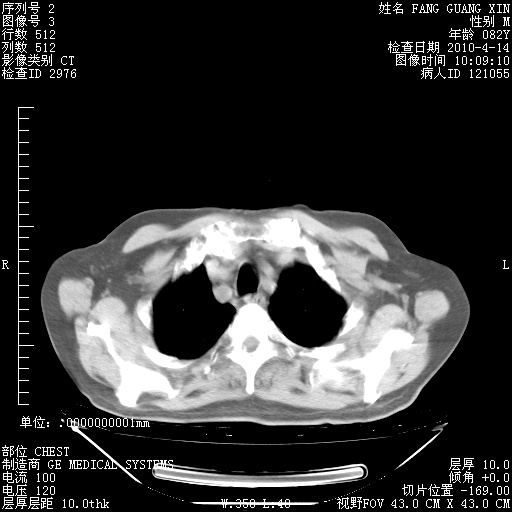

4月14日肺部CT

肺部CT平扫未见异常。